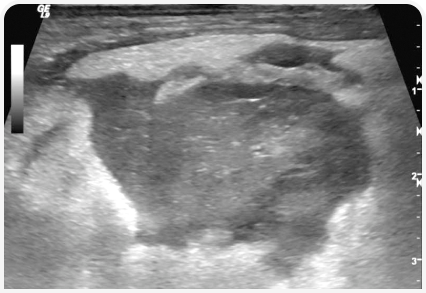

Диагностика панкреатита

Пациент: Фантик, йоркширский терьер, 6 лет

Жалобы: Однократная рвота, отказ от еды, прижимает живот.

Диагноз: увеличение поджелудочной железы, снижение эхогенности, контуры размыты, реактивное скопление жидкости вокруг. Картина острого панкреатита. Анализы (cPLI) подтвердили диагноз.

Что дало УЗИ: позволило быстро подтвердить воспаление поджелудочной железы и исключить другие причины боли в животе (например, инородное тело или заворот кишок).

Результат: Госпитализация, инфузионная терапия, голодная диета, обезболивание. Через 5 дней — восстановление аппетита, нормальное поведение. Переведён на низкожирный рацион. Полное выздоровление.